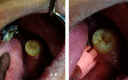

Figures